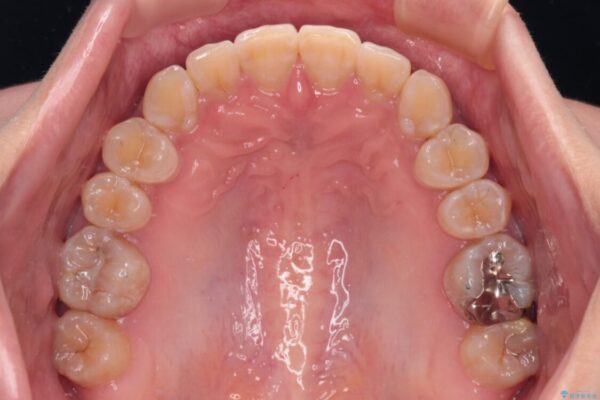

治療後

• 【モニター】下顎前歯のデコボコをインビザラインできれいに 治療後画像

治療前、下顎前歯のデコボコが集中しており、奥歯の咬み合わせは、上顎に対して下顎が前方位にある状態でした。下顎の歯列を後方へ移動させる治療はインビザラインの得意とするところですので、1年程度で無事に治療を終えることができました。